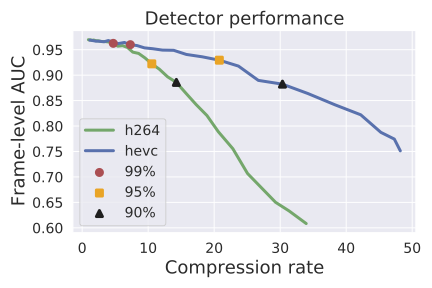

Compression rates: Figure 1 (left) shows the distribution of compression rates on colonoscopy videos for H264 and HEVC by QP value. At QP 51 (the highest compression rate for both classical codecs), HEVC achieved significantly more compression: the 25th, 50th, and 75th percentile compression rates were (43.6, 51.8, 56.5) for HEVC and (28.3, 39.8, 44.5) for H264.

Compression quality: Figure 1 (middle) shows the compression rate versus frame quality distribution for H264 and HEVC. Importantly, we see that H264 and HEVC compress the most medically relvant frames statistically significantly worse: treating each QP value separately, a two-sided Kolmogorov-Smirnov test between distribution of PSNR-CbCr shows that the frame quality is lower for polyp frames than for all frames. For each QP value, , , H264 (HEVC) maximum p-value over all tests is (), mean test statistic (). For the same test with PSNR-Y, see the Appendix. Figure 2 top two rows show the lowest quality compressed frames inside the body according to PSNR-CbCr, with and without polyps (for the absolute worst quality compressed frames, see the Appendix).

Detector performance: Figure 1 (right) shows the polyp detector performance as a function of compression rate. Videos can be compressed by factors of 4.7x and 7.3x before dropping below 99% the base performance for H264 and HEVC respectively, 10.6x and 20.8x for 95%, and 14.3x and 30.4x for 90%. In addition to getting better frame quality and higher compression rates, the detector performs 0.057 AUC better and a 29% relative improvement111relative improvement defined as on HEVC videos compared to H264, as the same compression rate. The same holds in the “practical" regime of compression rates that achieve at least 95% the AUC of the original model: AUC is on average 0.26 AUC improved with a 23% relative improvement in AUC.